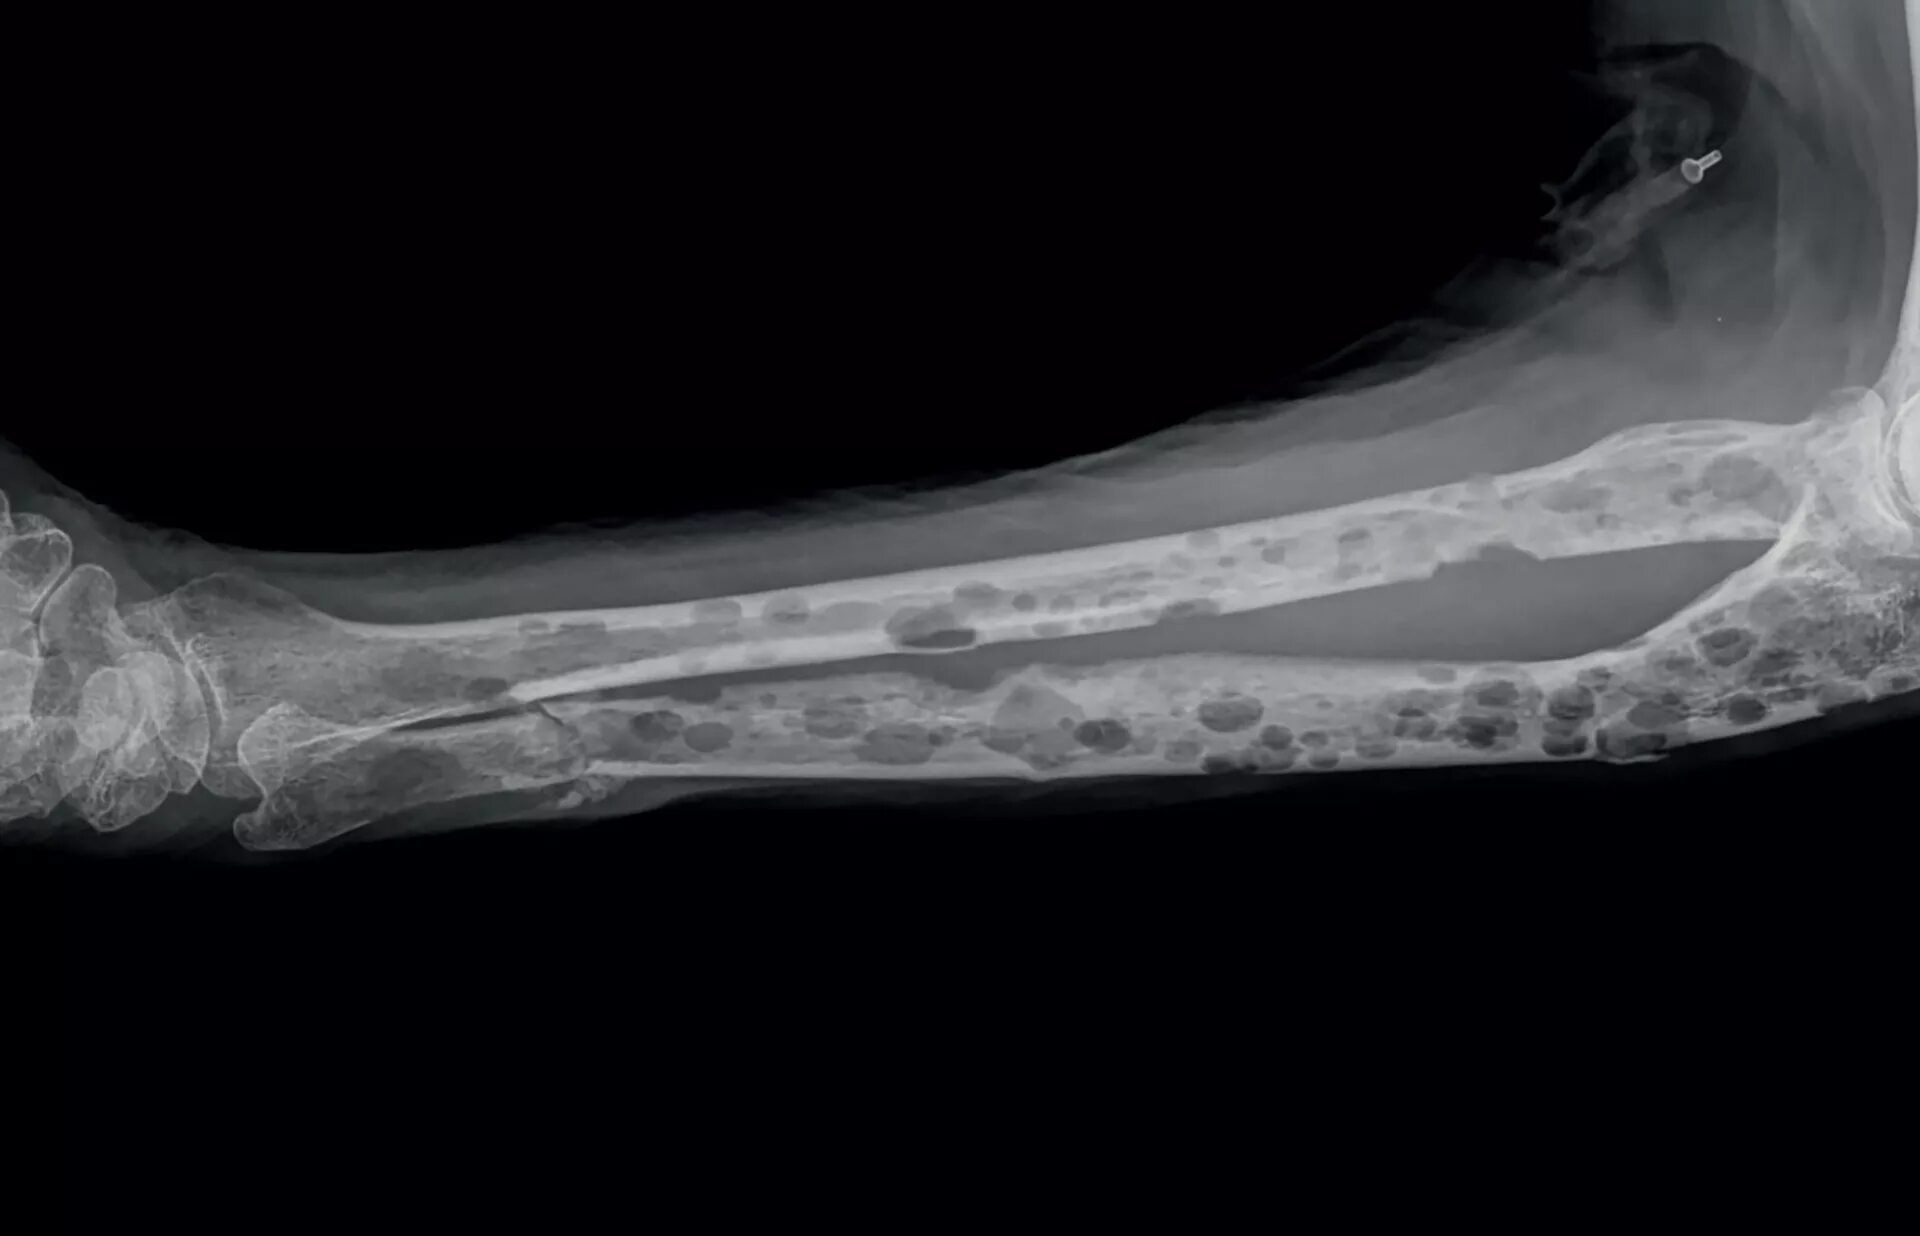

Метастазы в костном мозге